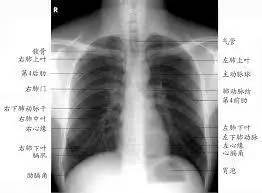

X线胸片

看胸片秘诀:

观察胸廓是否对称, 两侧肋骨肋间隙是否正常;两肺纹理是否清晰,未见明显实质性浸润;两侧肺门纵膈未见明显异常;心脏大小形态在正常范围;膈肌平滑,双侧肋膈角锐利。